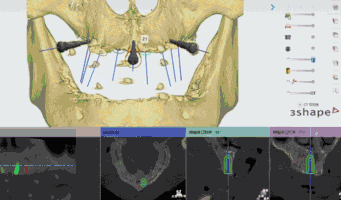

为了能让广大的合作伙伴学习数字化口内扫描技术,特别是在种植方面的应用,靖佳齿科联合上海复星牙科一起带来行业内领先的3Shape口内扫描仪,通过理论讲解+实战操作,一步一步教会大家掌握数字化种植(导板)的操作技术,让大家快人一步,确立自身的竞争优势,同时可以最大限度的发挥出口扫的使用价值。

精彩案例: